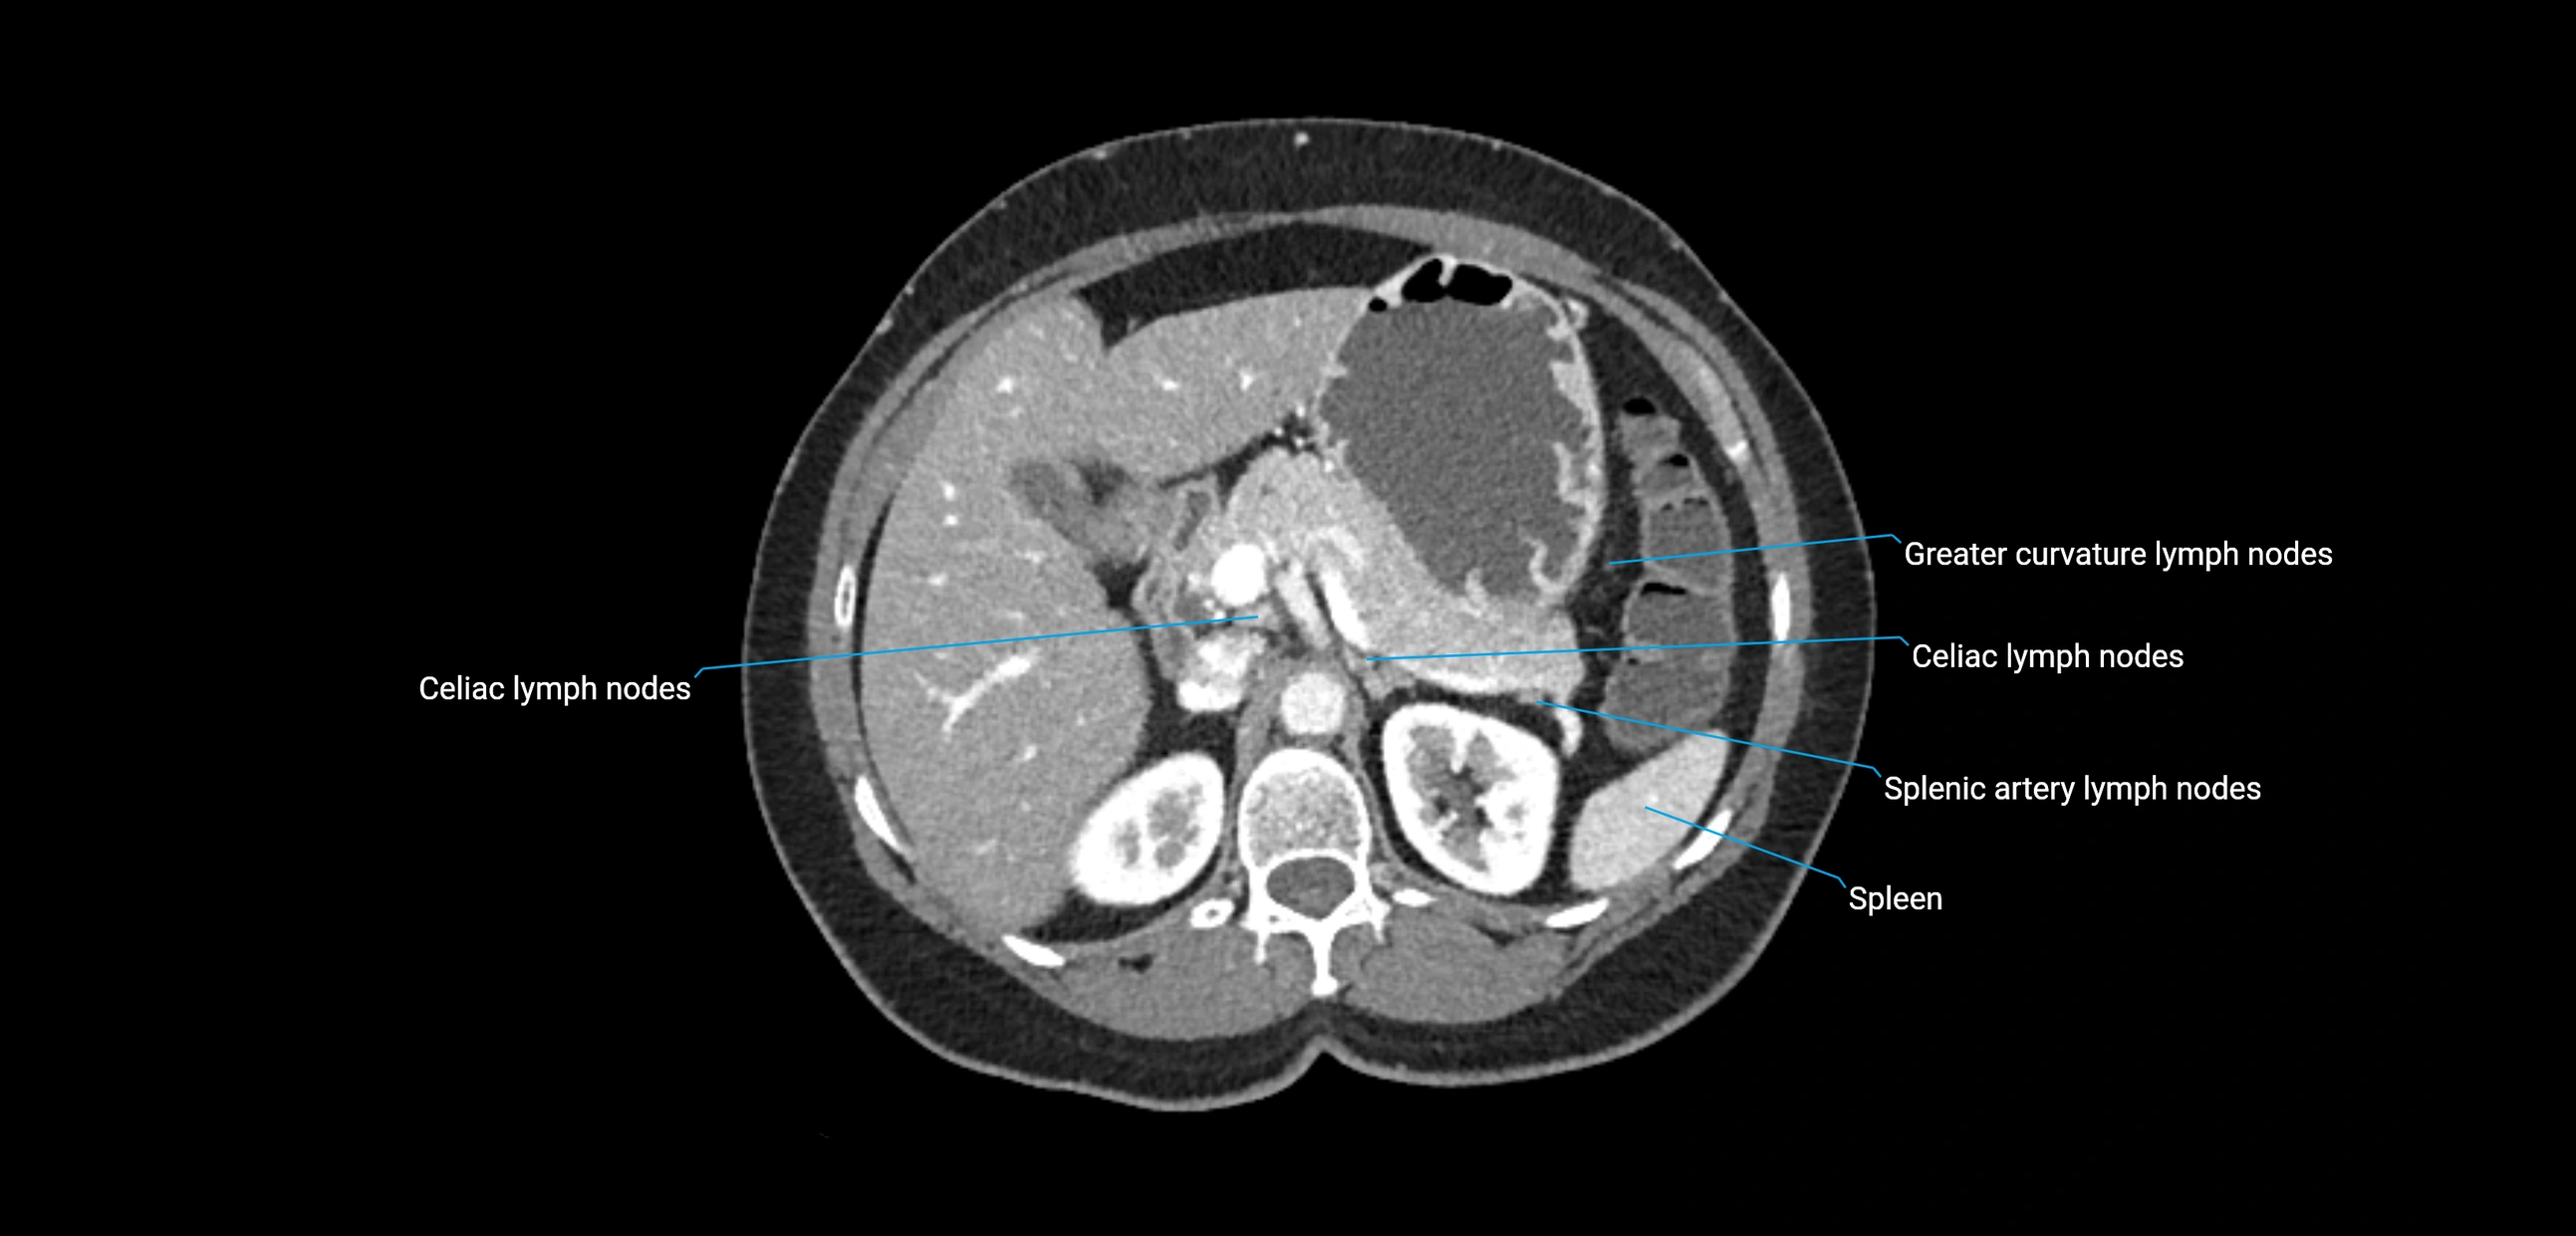

CT image

image